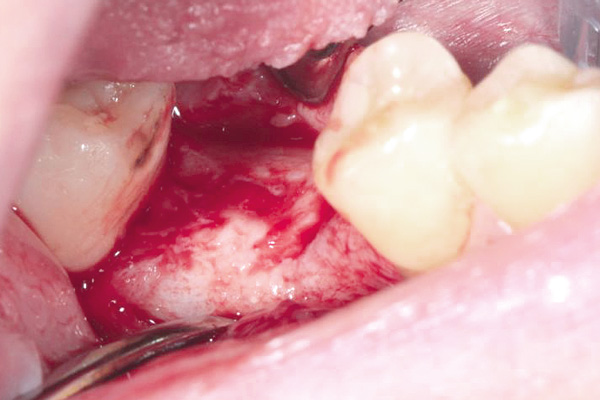

Situation after tooth extraction.